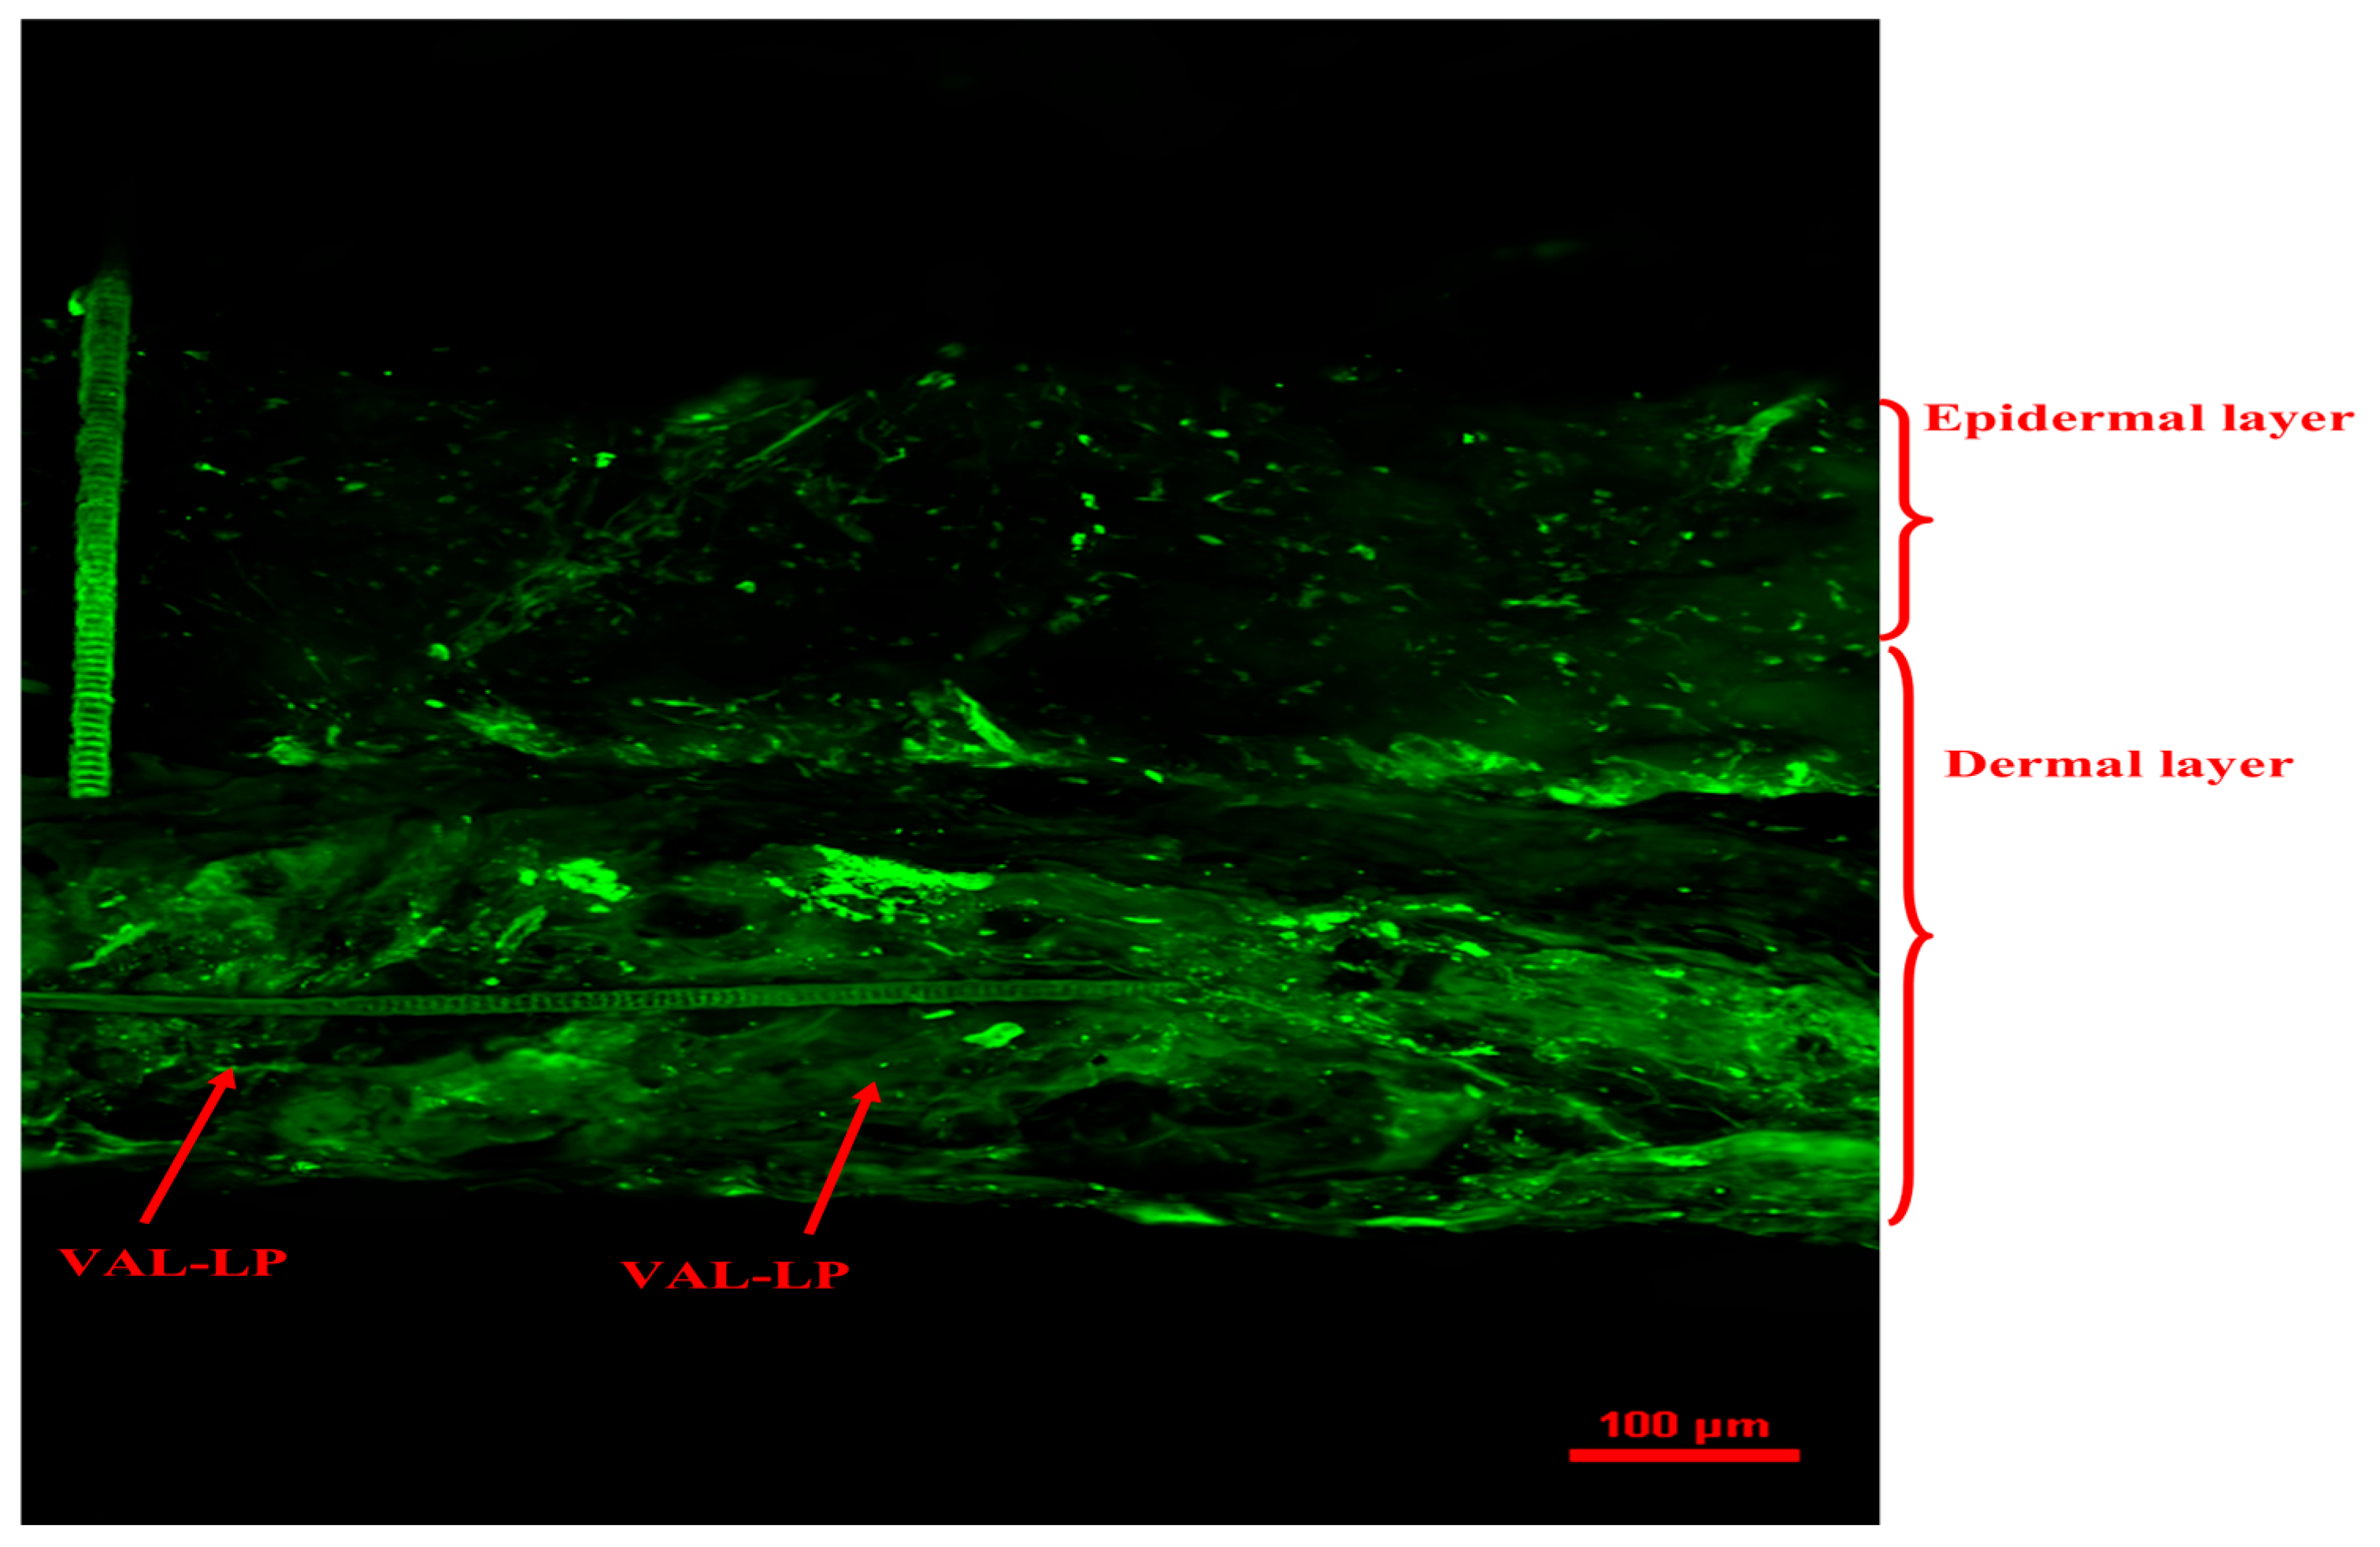

3.1.9. Confocal Laser Scanning Microscopy (CSLM)

SEM and CSLM Analysis of Rat Skin Punctured with VAL-LP-DMNs